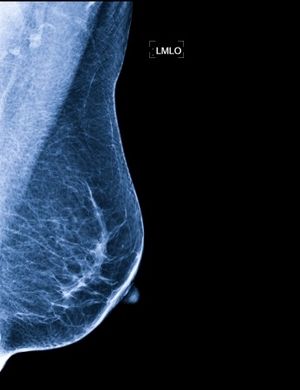

- diagnostykę USG w zakresie nowotworów piersi, tarczycy, węzłów chłonnych,